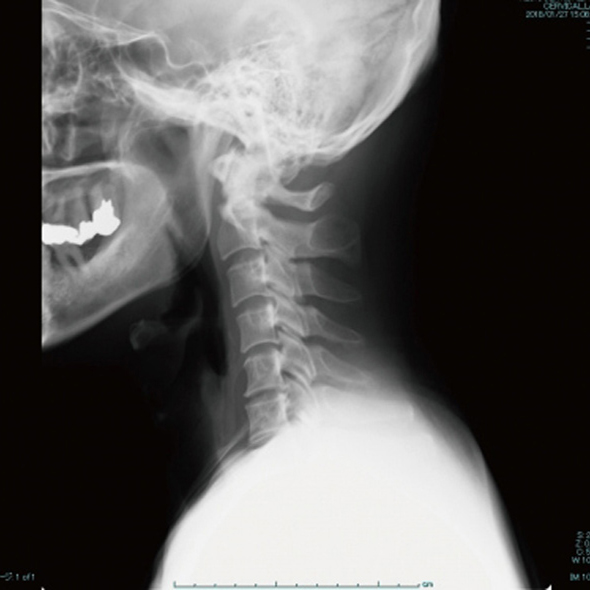

むち打ち症(正式名:頚椎捻挫)は、交通事故などで首がムチのようにしなることで起こります。

首の靭帯や関節が損傷し、正面・側面・追突などで発症します。治療が不十分だと、後遺症として長期間痛みが残ることがあります。

交通事故治療は画像診断が不可欠です。

レントゲンでは、骨折の症状に影響を与えるような経年性変化(加齢変化)を診断します。